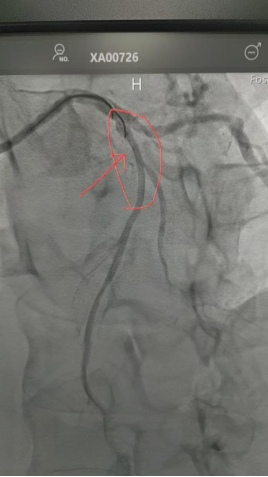

造影显示该患者为近端次全闭塞——几乎堵死了。手术团队精准操作,植入1枚药物球囊后,该患者症状立即缓解。